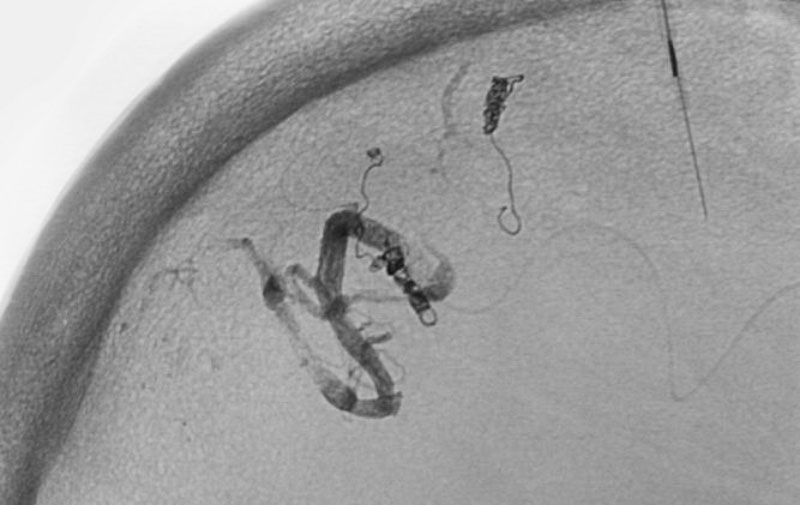

くも膜下出血

左中大脳動脈瘤破裂

40代

救急外来

No.1596 手術中